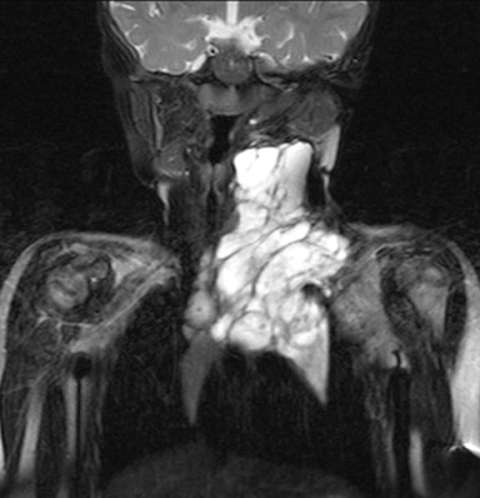

Coronal MRI STIR images demonstrating large left neck macrocystic lymphatic malformation